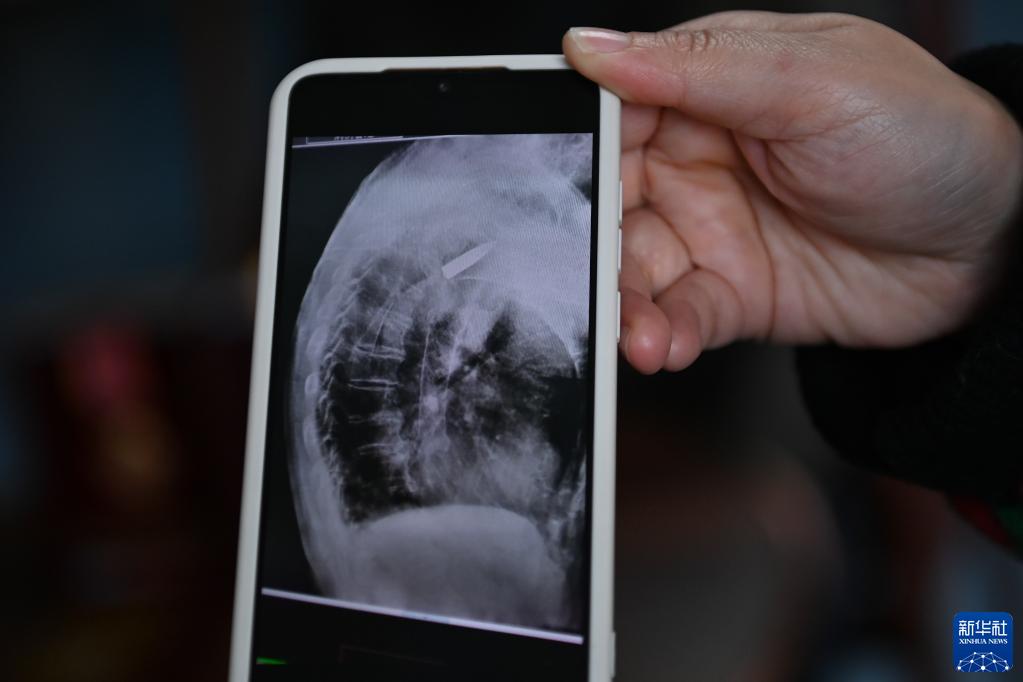

2022年11月11日上午,浙江省平湖市第一人民醫院,消化科內鏡室主任醫師王明友正在為一位吞咽困難的96歲老人做食道支架置入手術(shù)。突然,醫生的眉頭緊皺起來(lái):在X射線(xiàn)下,發(fā)現老人右側肩膀里居然有一顆長(cháng)約3.5厘米的子彈!

醫院的放射線(xiàn)視覺(jué)指引圖像顯示,羅錦文老人右側肩膀里有一顆長(cháng)約3.5厘米的子彈(3月2日攝)。新華社記者 黃宗治 攝

2022年,平湖市第一人民醫院在給老人做食道支架置入手術(shù)時(shí),X射線(xiàn)下清晰地看到老人肩膀里有顆長(cháng)約3.5厘米的子彈。而這顆子彈,早已與老人的骨頭粘在了一起,無(wú)法取出。